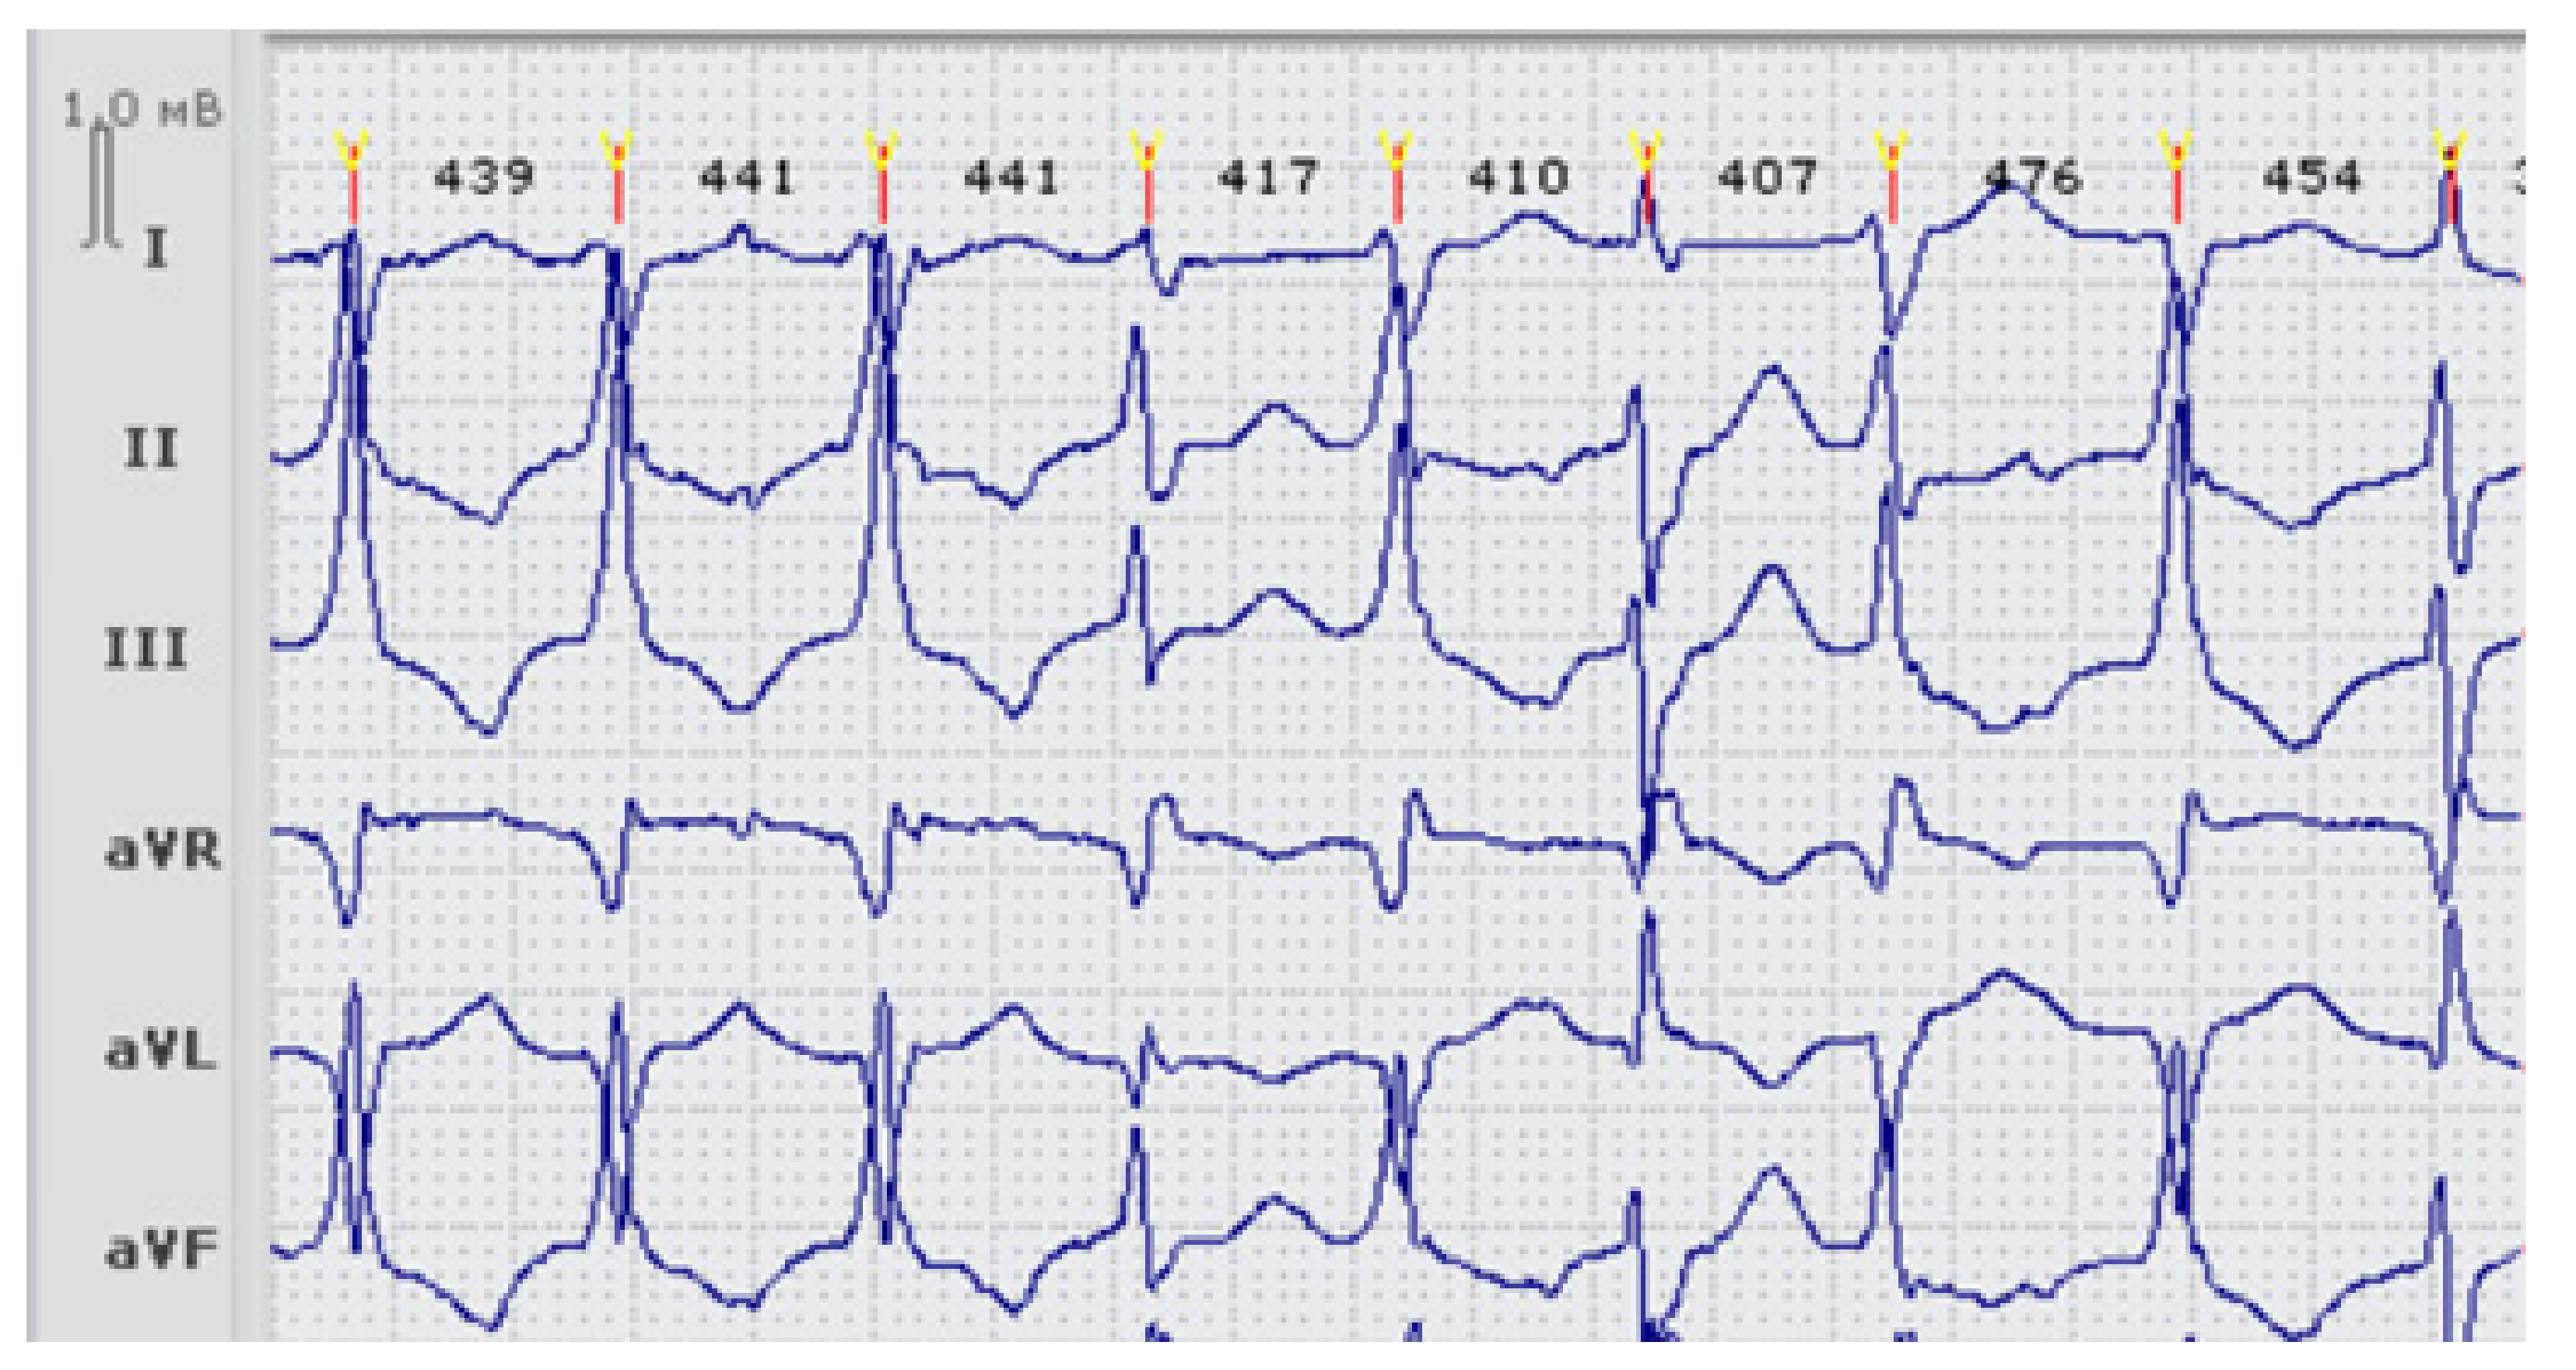

| LQTS_96 | 29 | p.Arg67Trp (V) | De novo | Decreased [9] | 494–500 | 540 | Yes | + | VT, PVB, bigeminy | BB, ICD |

| LQTS_139 | 15 | p.Val93Ile (III), p.Arg132Trp in SCN3B (III) | Inherited | Increased [11,13] | 449–480 | 568 | No | no | no | BB recommended (refused) |

| LQTS_33 | 23 | p.Arg218Gln (V), p.Thr983Ile in KCNH2 (III) | DNA samples from parents unavailable | Decreased [14] | 600–620 | 650 | Yes | + | PVB, paroxysmal VT, VF, appropriate shocks | BB, ICD |